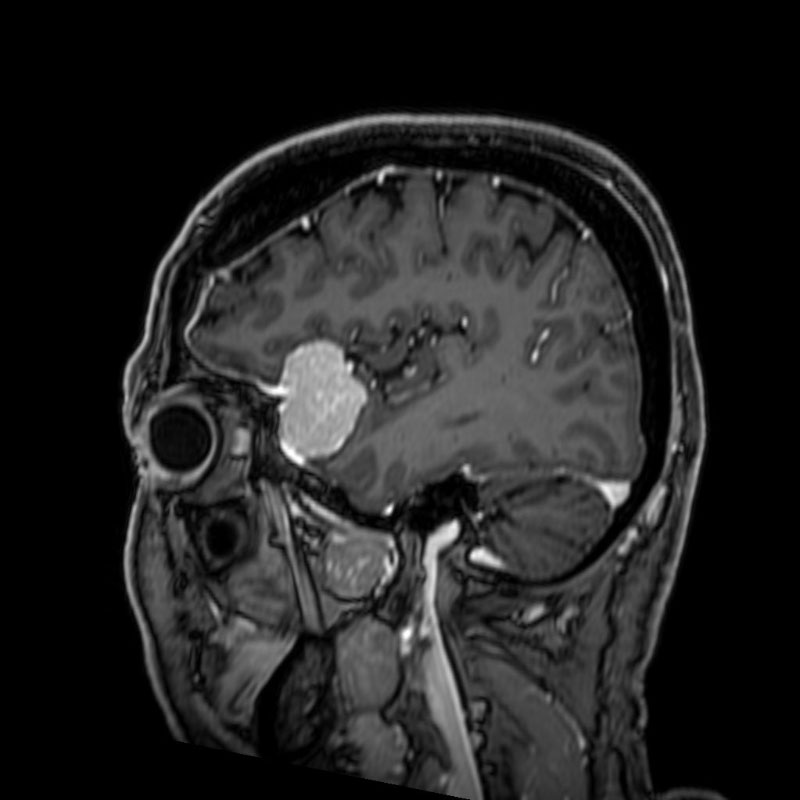

626

'25年4月

50代

右聴神経腫瘍

頭蓋内腫瘍摘出術

No.’25_28 手術前1

No.’25_28 手術前2